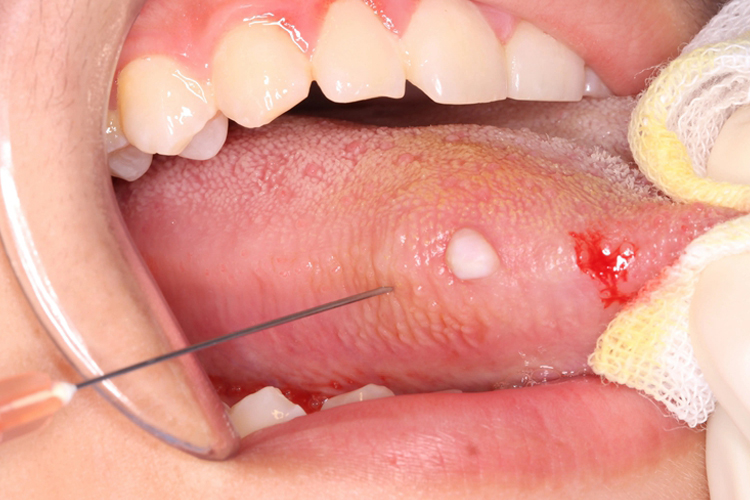

舌侧乳头状瘤多表现为上皮组织高度增生,鳞状上皮向外过度生长形成乳头,呈圆形或椭圆形上皮团块,中心有疏松而富有脉管的结缔组织,一般无自觉症状。

乳头状瘤